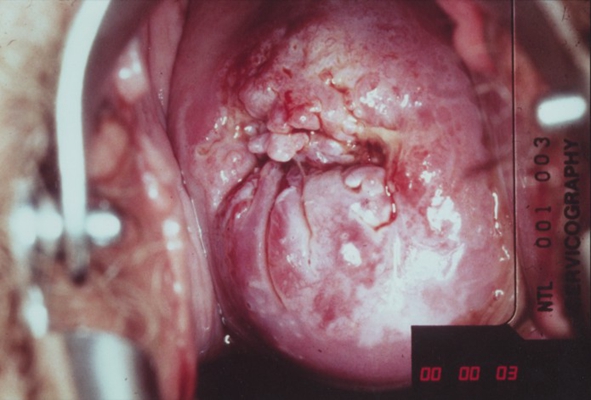

子宮頸癌圖片

宮頸癌

宮頸癌

宮頸癌

宮頸癌

宮頸癌

宮頸癌

宮頸癌

宮頸癌

宮頸癌

宮頸癌

宮頸癌

宮頸癌

宮頸癌

宮頸癌

宮頸癌

宮頸癌

宮頸癌

宮頸癌

宮頸癌

宮頸癌